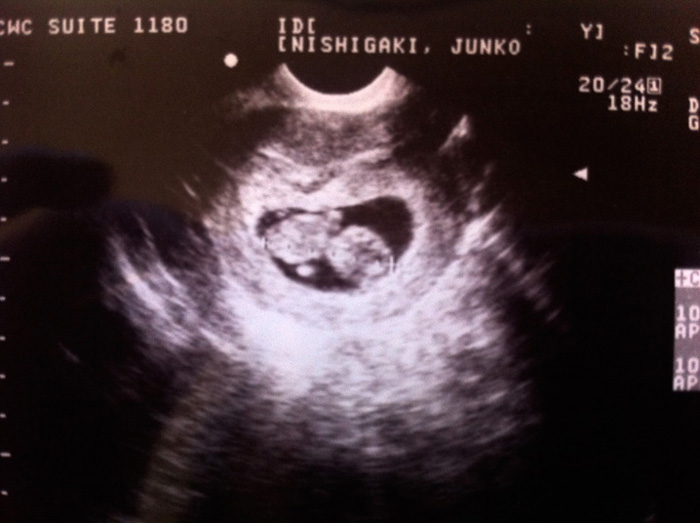

超音波でみたら、前回の卵型から人間の型に変わっていた。まだ3.3cmなのに、両手両足を一生懸命動かしていてとても可愛かった。ドクターに「So active baby!!」と言われる。現在10週と2日、予定日は4月1日♪